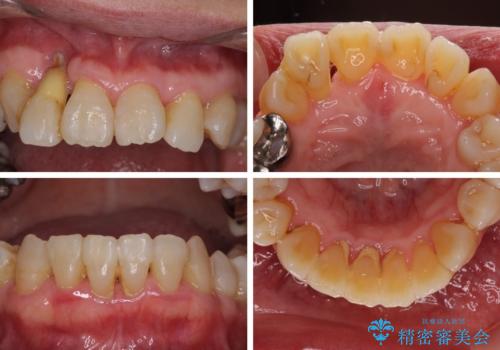

- 歯の欠損や歯肉からの出血などを気にして来院された患者様です。

診査の結果、歯周病であることが分かり、抜歯が必要な歯も見受けられました。

骨造成やインプラント、歯周外科、歯肉移植、矯正など、多くの処置を組み合わせて治療を行うこととしました。

数多くの外科処置を行ったため、治療期間は長期間となりました。

一方、外科処置をしっかりと行ったことで、歯周病の状態は改善され、安定した状態にしあげることができました。